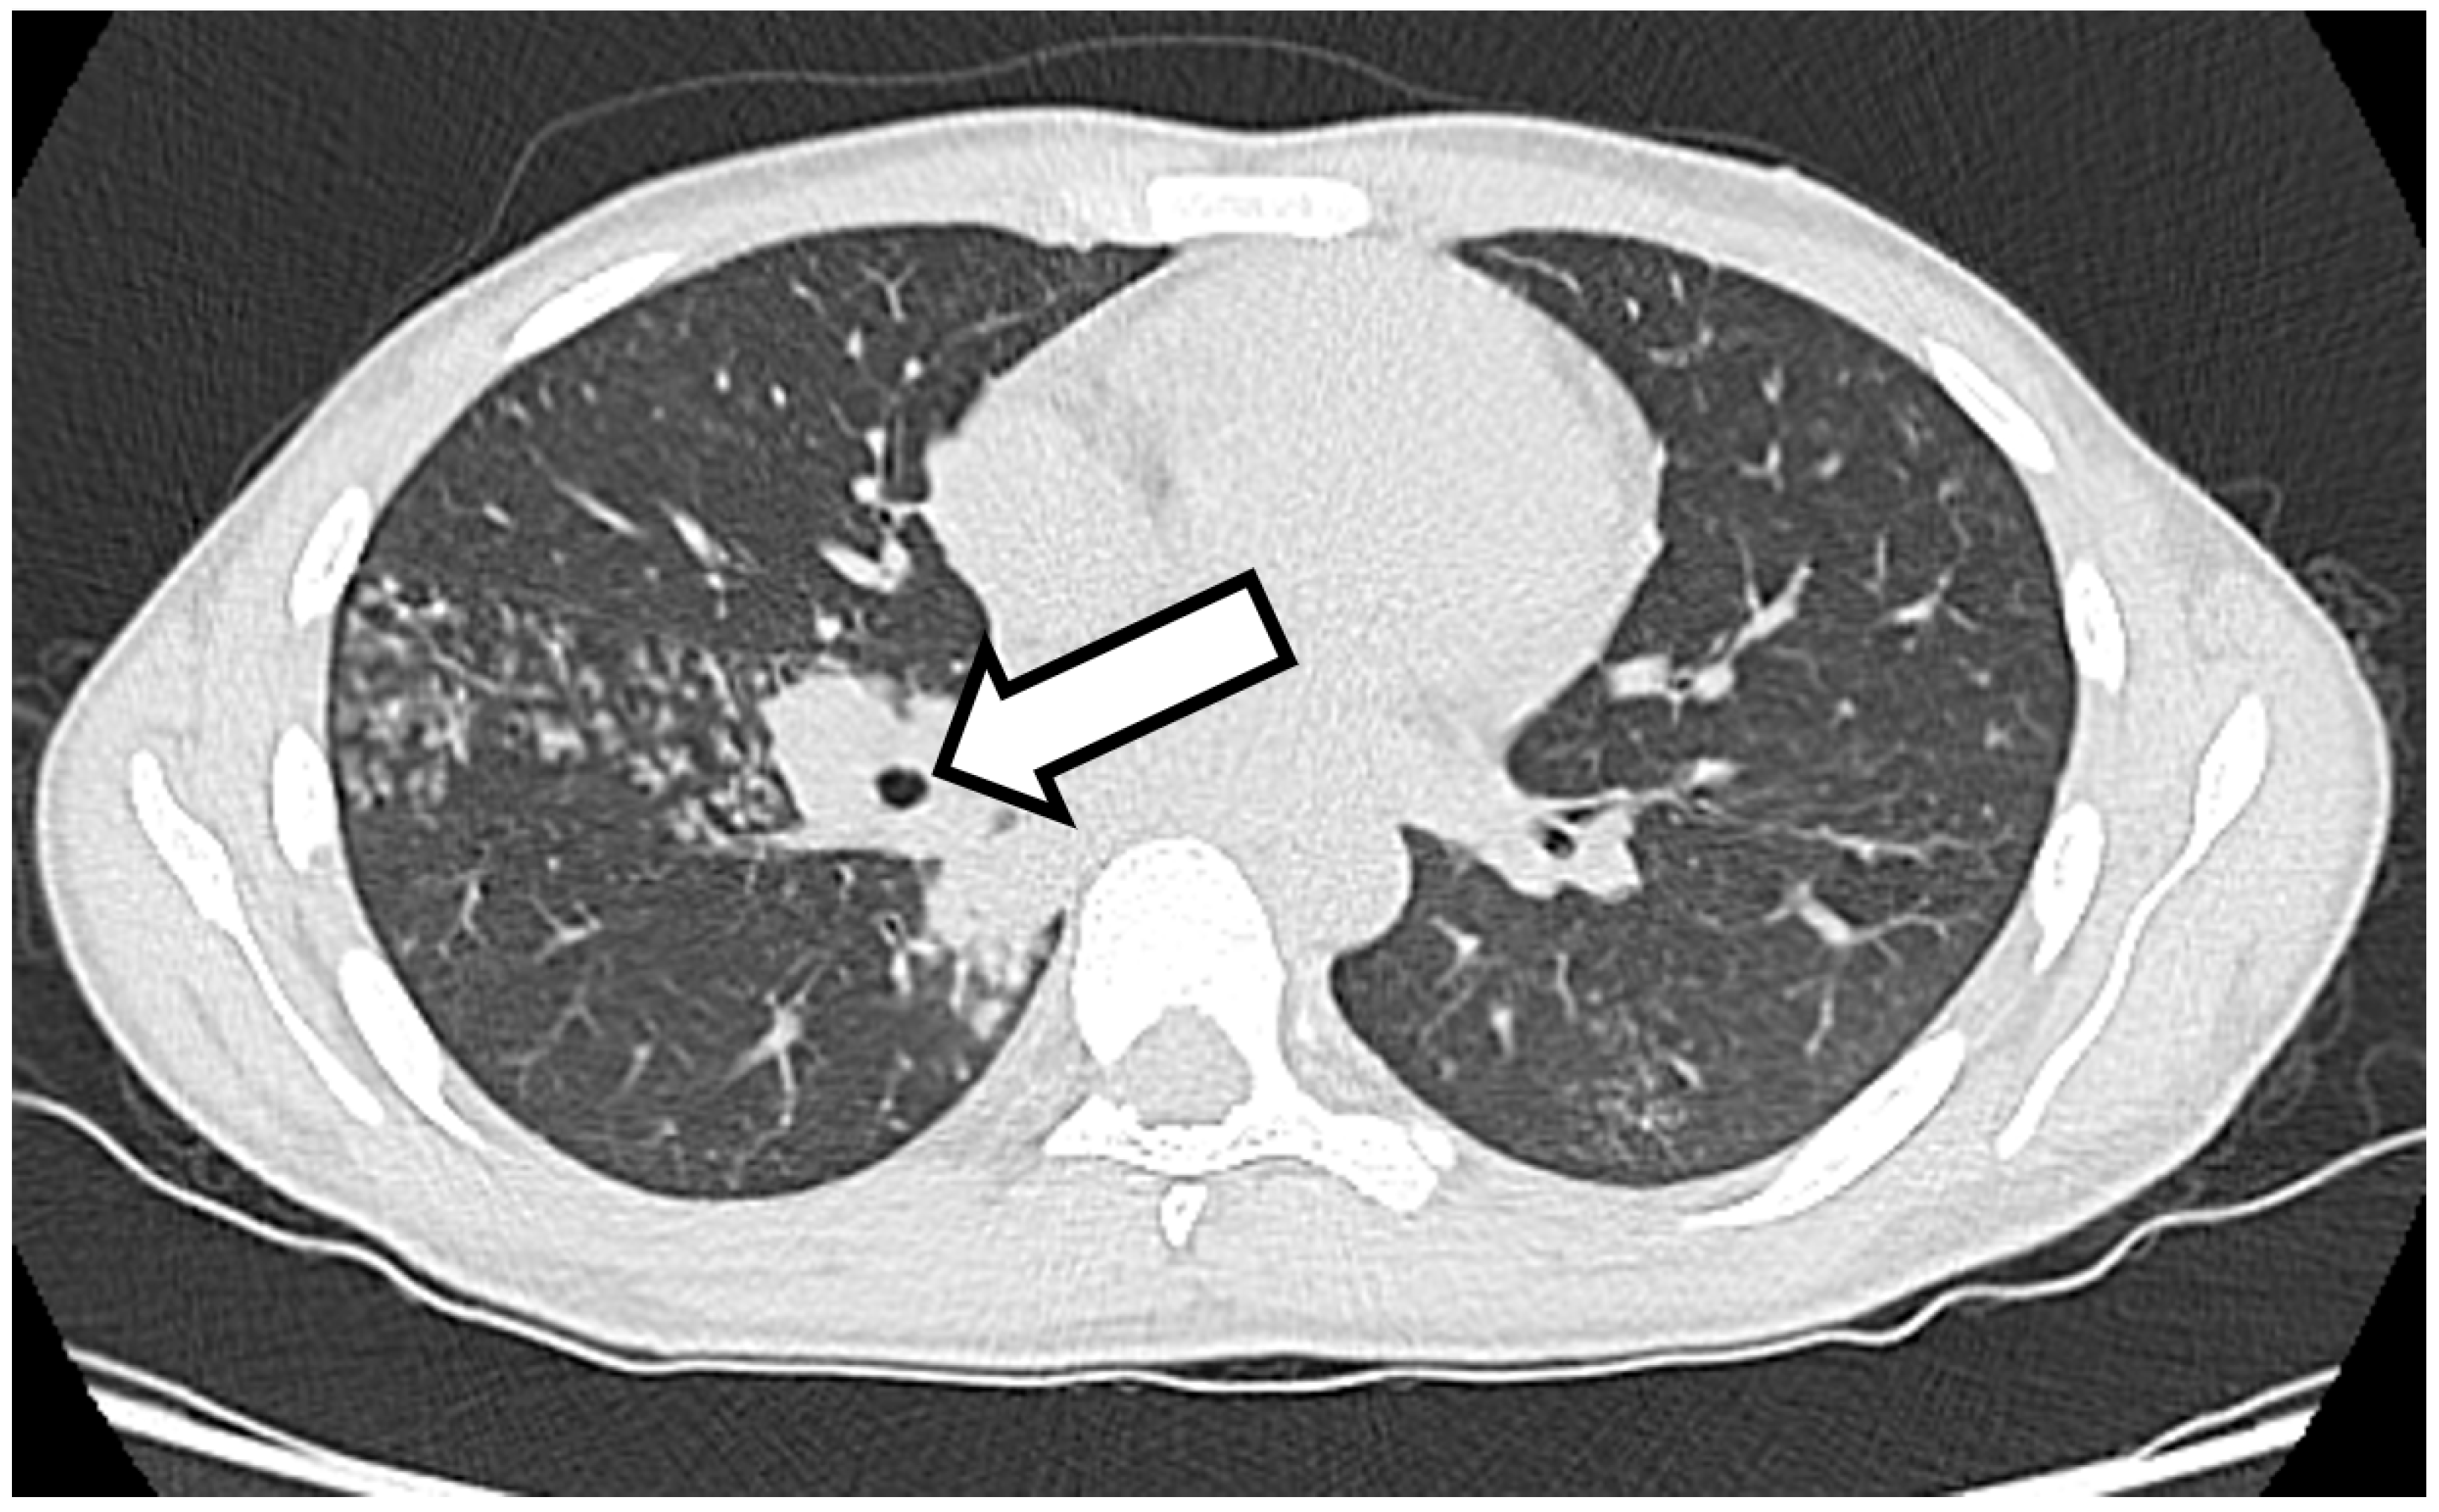

The Appearance of Osteomyelitis of the Foot and Disseminated Subcutaneous Abscesses During Treatment for Disseminated Tuberculosis Infection in an Immunocompetent Patient: Case Presentation of a Paradoxical Reaction and Literature Review

2. Case Presentation